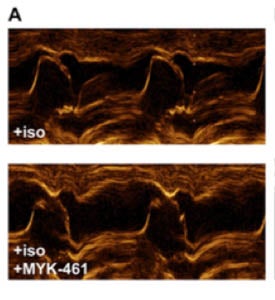

image with two panels comparing obstructed and clear pathways for blood flow

One image of many in Dr. Stern’s published article that shows clearer pathways for blood flow after MYK-461 treatment (bottom panel) in cats with hypertrophic cardiomyopathy.

Specifically, in the study, treatment with MYK-461 eliminated obstruction in the left ventricle in five cats with HCM. This means that the novel drug may help keep excessive growth of the heart’s walls at bay — without surgery or interventional procedures — so the heart can pump and blood can flow easily and efficiently. The hope is that because of improved heart function, cats with HCM may enjoy a longer lifespan and high quality of life during that time.